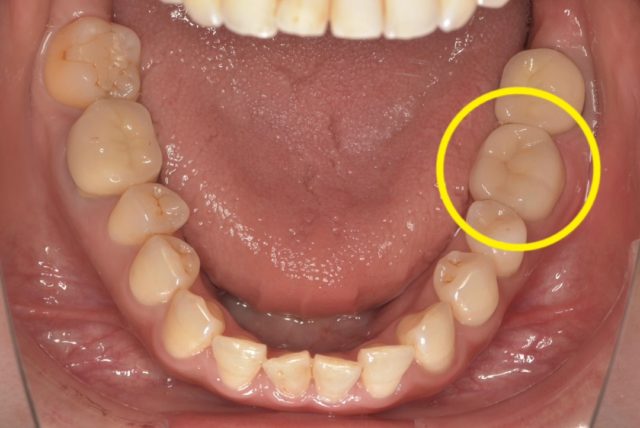

根管治療・破折リーマー除去

被せが外れてしまい…

根管治療について

根管の中にで折れた器具が?破折リーマー除去について